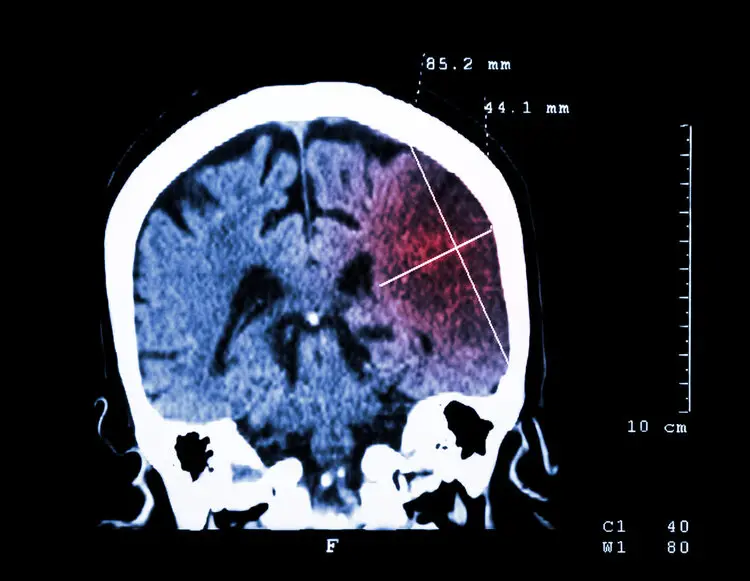

经检查大爷血压高达180mmHg,结合大爷有高血压病史,又出现口角歪斜、肢体无力等表现,最后诊断为脑出血,需要立刻手术降压。医生提醒这已经不是第一个因为高血压引发脑出血的病例了。